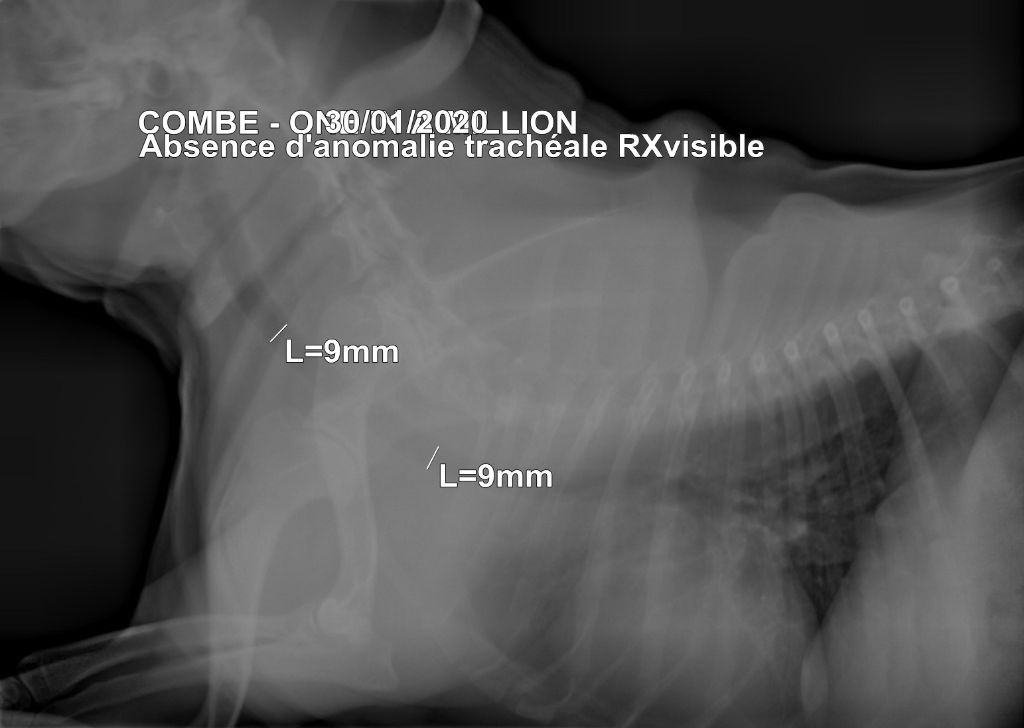

Dépistage cardiaque : Saine HUU : ''Clear'' héréditaire Test ECVO( yeux) : Indemne de toutes maladies occulaires Trachée : Saine luxation rotules : 0/0 |